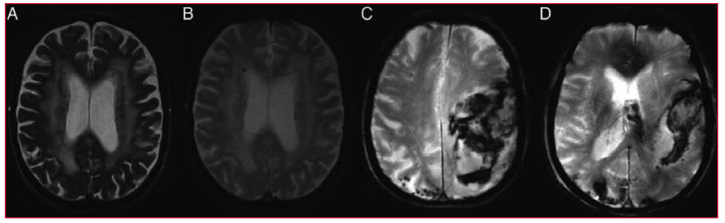

RNM cerebral para adaptar la anticoagulación

Otro artículo de revisión analizó el valor de la imagenología cerebral con RNM para adaptar la terapia anticoagulante(59). Se encontró que es frecuente observar infartos cerebrales silentes en pacientes con FA(60,61), dependiendo de la edad del paciente y del tipo de FA. La presencia de microsangrados cerebrales (MSC), que se hallan fre- cuentemente en pacientes con FA sin antecedentes de accidente cerebrovascular, deben ser considerados como un riesgo de sangrado intracraneano en caso de anticoagular al paciente. Sin embargo, se necesitan estudios de gran tamaño para confirmar esta observación. El número y la ubicación de los MSC se ven afectados por las puntuaciones de CHADS2 y CHA2DS2Vasc. Esto es fundamentalmente debido al efecto de los factores de riesgo vascular (figura 5)(62).